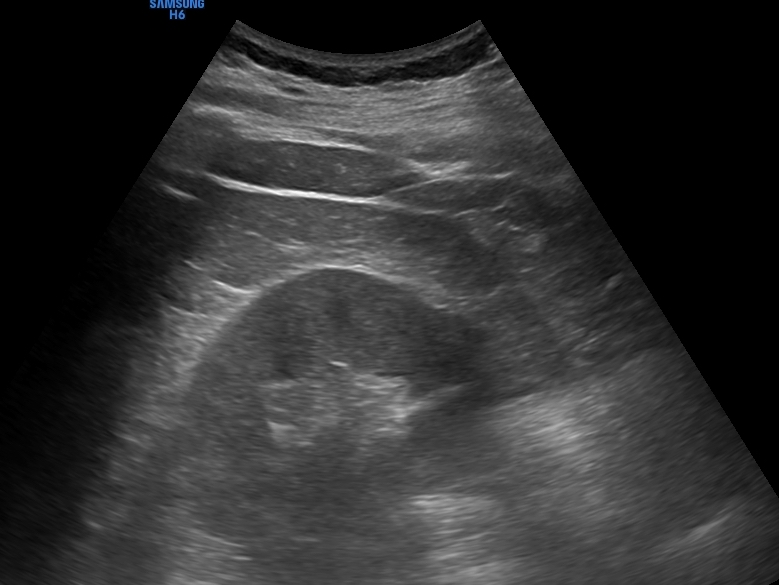

Persistiendo el dolor, se realiza ecografía clínica objetivándose: vejiga con abundante contenido urinario, con sensibilidad a la palpación y sin deseo miccional. Riñones de morfología y ecoestructura normal, sin signos de hidronefrosis. Hígado y vesícula sin alteraciones, sin litiasis y Murphy ecográfico negativo.

Ante los hallazgos, se plantea la posibilidad de retención aguda de orina (RAO). Este caso ilustra cómo la presentación clínica de la RAO puede simular un cólico nefrítico u otras causas de dolor abdominal agudo.

La ecografía clínica resultó decisiva al identificar una vejiga distendida sin signos de obstrucción a nivel renal, permitiendo un diagnóstico rápido y un tratamiento inmediato.